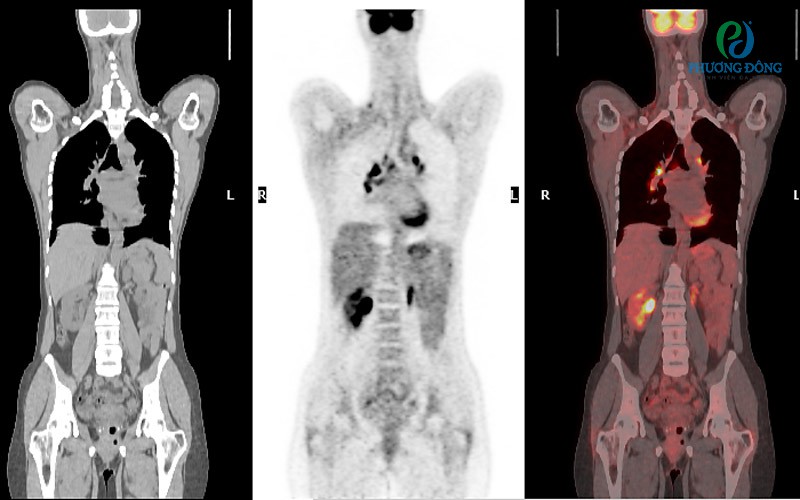

Hình ảnh cơ thể được chụp từ ba góc độ khác nhau bằng máy quétHình ảnh cơ thể được chụp từ ba góc độ khác nhau bằng máy quét

Ghi chú:

• Hình bên trái là ảnh CT đơn thuần .

• Hình ở giữa là ảnh PET đơn thuần.

• Hình bên phải là ảnh kết hợp giữa ảnh PET và CT.

• Các hình ảnh màu được mã hóa để làm nổi bật các vùng chuyển hóa bất thường. Đây thường là dấu hiệu của một khối u.